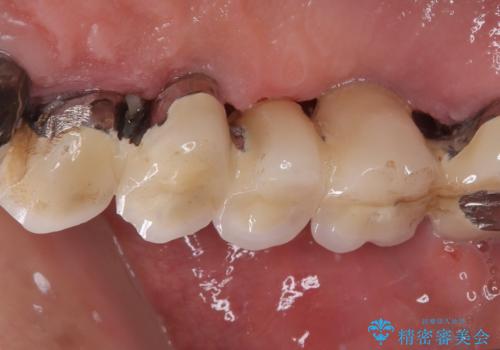

- 奥歯がぐらぐらして噛めないとのことで来院された患者様です。

ブリッジの土台となっている歯は全て抜歯が必要な状態であったため、事前に仮歯を用意して、極力抜歯と同時にインプラントを埋入し、速やかに仮歯を装着して噛めるように処置を進めて行くこととしました。

後方2本を先に埋入し、即日で仮歯を装着しましたが、徐々にインプラントが骨内で緩んでしまい、手前のインプラント埋入時に再埋入することとなりました。